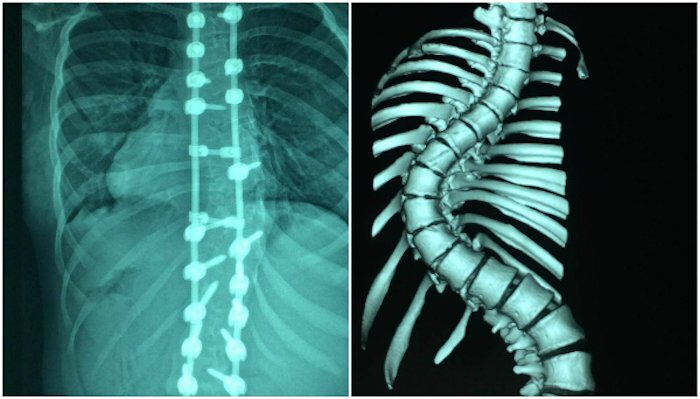

Nhiều năm bị cong cột sống, cô bé được bác sĩ mổ nắn thẳng lưng giúp tăng thêm 7 cm và có thể tự tin mặc áo dài đi học.